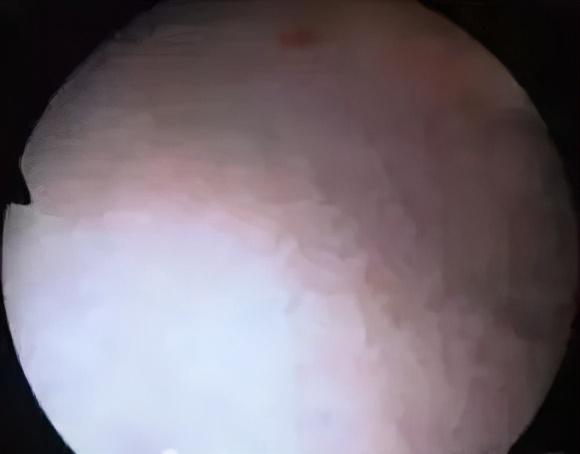

史托斯膀胱镜检查,是应用较为广泛的一种泌尿外科的内窥镜检查方法,是膀胱、尿道疾病,尤其是女性宫颈癌、盆腔肿瘤等疾病,也可用于膀胱结石碎石术、膀胱肿瘤电切术、输尿管结石套石术、输尿管扩张术等疾病的确诊金指标。尤其对一些较小的肿瘤,膀胱镜检查具有独特的优势,已成为泌尿外科医师的“第三只眼”。

膀胱结石

输尿管开口喷血

膀胱乳头状瘤

带蒂膀胱肿瘤